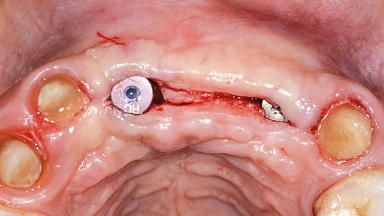

Replacement of Two Central Incisors and One Lateral Incisor with a Fixed Dental Prosthesis on Two Bone-Level Implants

A 38-year-old woman presented with an esthetically unacceptable fixed partial denture replacing teeth 11, 21, 22. She had lost these teeth due to trauma when she was a child. The patient was not in pain but very concerned based on her previous experience that dental treatments had never satisfied her esthetic expectations. She was in good general health and reported no regular medications. No periodontal disease was noted despite the fact that the buccal flange of the prosthesis impeded cleaning of the tooth abutments. The patient did not smoke and complied with home maintenance requirements, as evidenced by her good oral hygiene status.